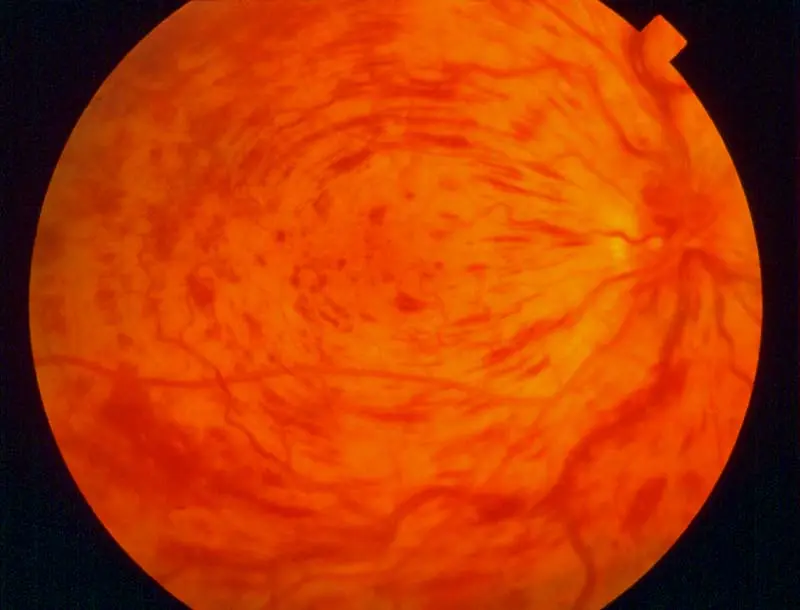

Retinitis Pigmentosa or Pigmentary retinopathy

- Pigmentation in periphery

Symptoms:

- Night blidness, Tunnel vision

- Gradual painless vision loss

- Photopsia

Fundus - three findings

- Optic disc wax color,

- Bone spicule pigment deposition

- *Attenuation or narrowing blood vessels